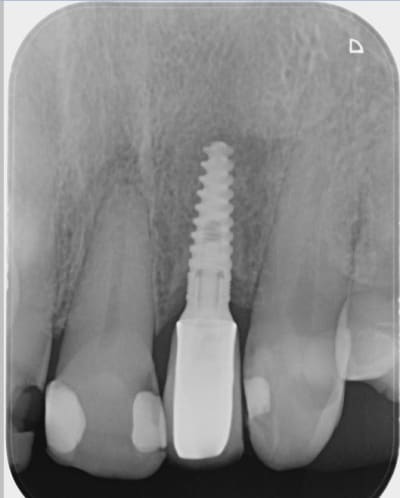

Quelqu'un peut-il me dire de quel implant il s'agit.

Je soupçonne très fortement un MIS Seven, sans doute un 3.30 (et meme un 11.5mm ) mais je ne suis sur de rien.

Ça semble bien être un seven